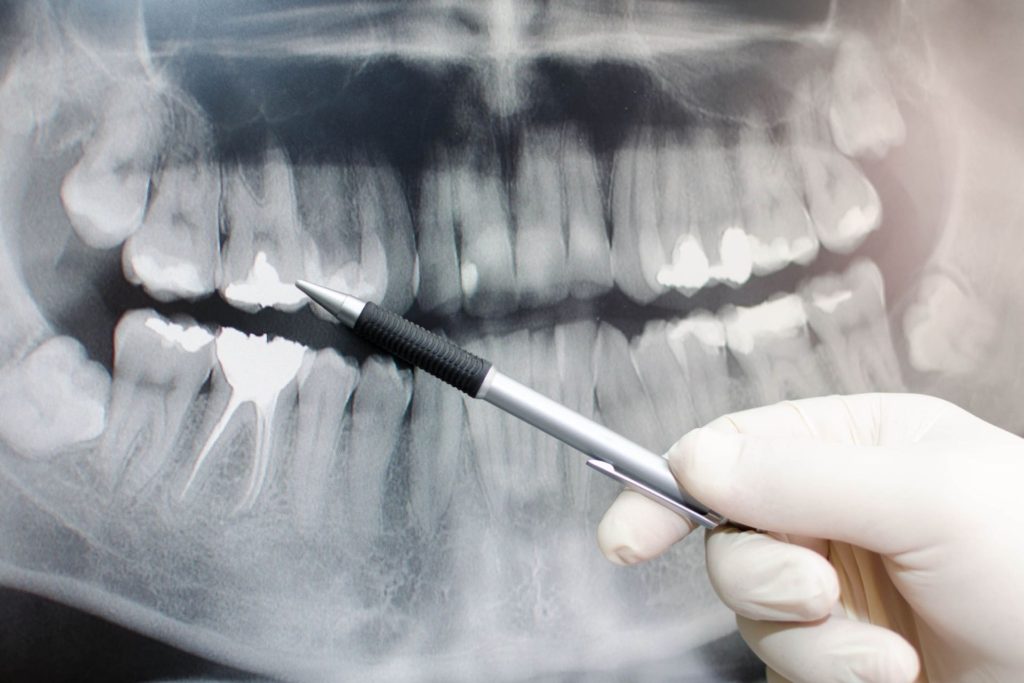

歯槽膿漏(歯周病)とは骨の病気です。

あなたの歯を支えている骨が

どんどん溶けてなくなっていく

病気です。

歯周病はいわば「骨の病気」です。

骨の病気ですので、診断にはまずはレントゲンの撮影が必要です。

もっと詳しく診断するにはCT装置による撮影を行い、

歯を支えている骨(歯槽骨)や顎の骨、

顎関節の状態まで確認することが必要になります。

歯は歯槽骨という骨に支えられています。

あなたの歯がまだしっかりとしてグラグラともしていないのは、

この歯を支えている骨がしっかりしているからなのです。